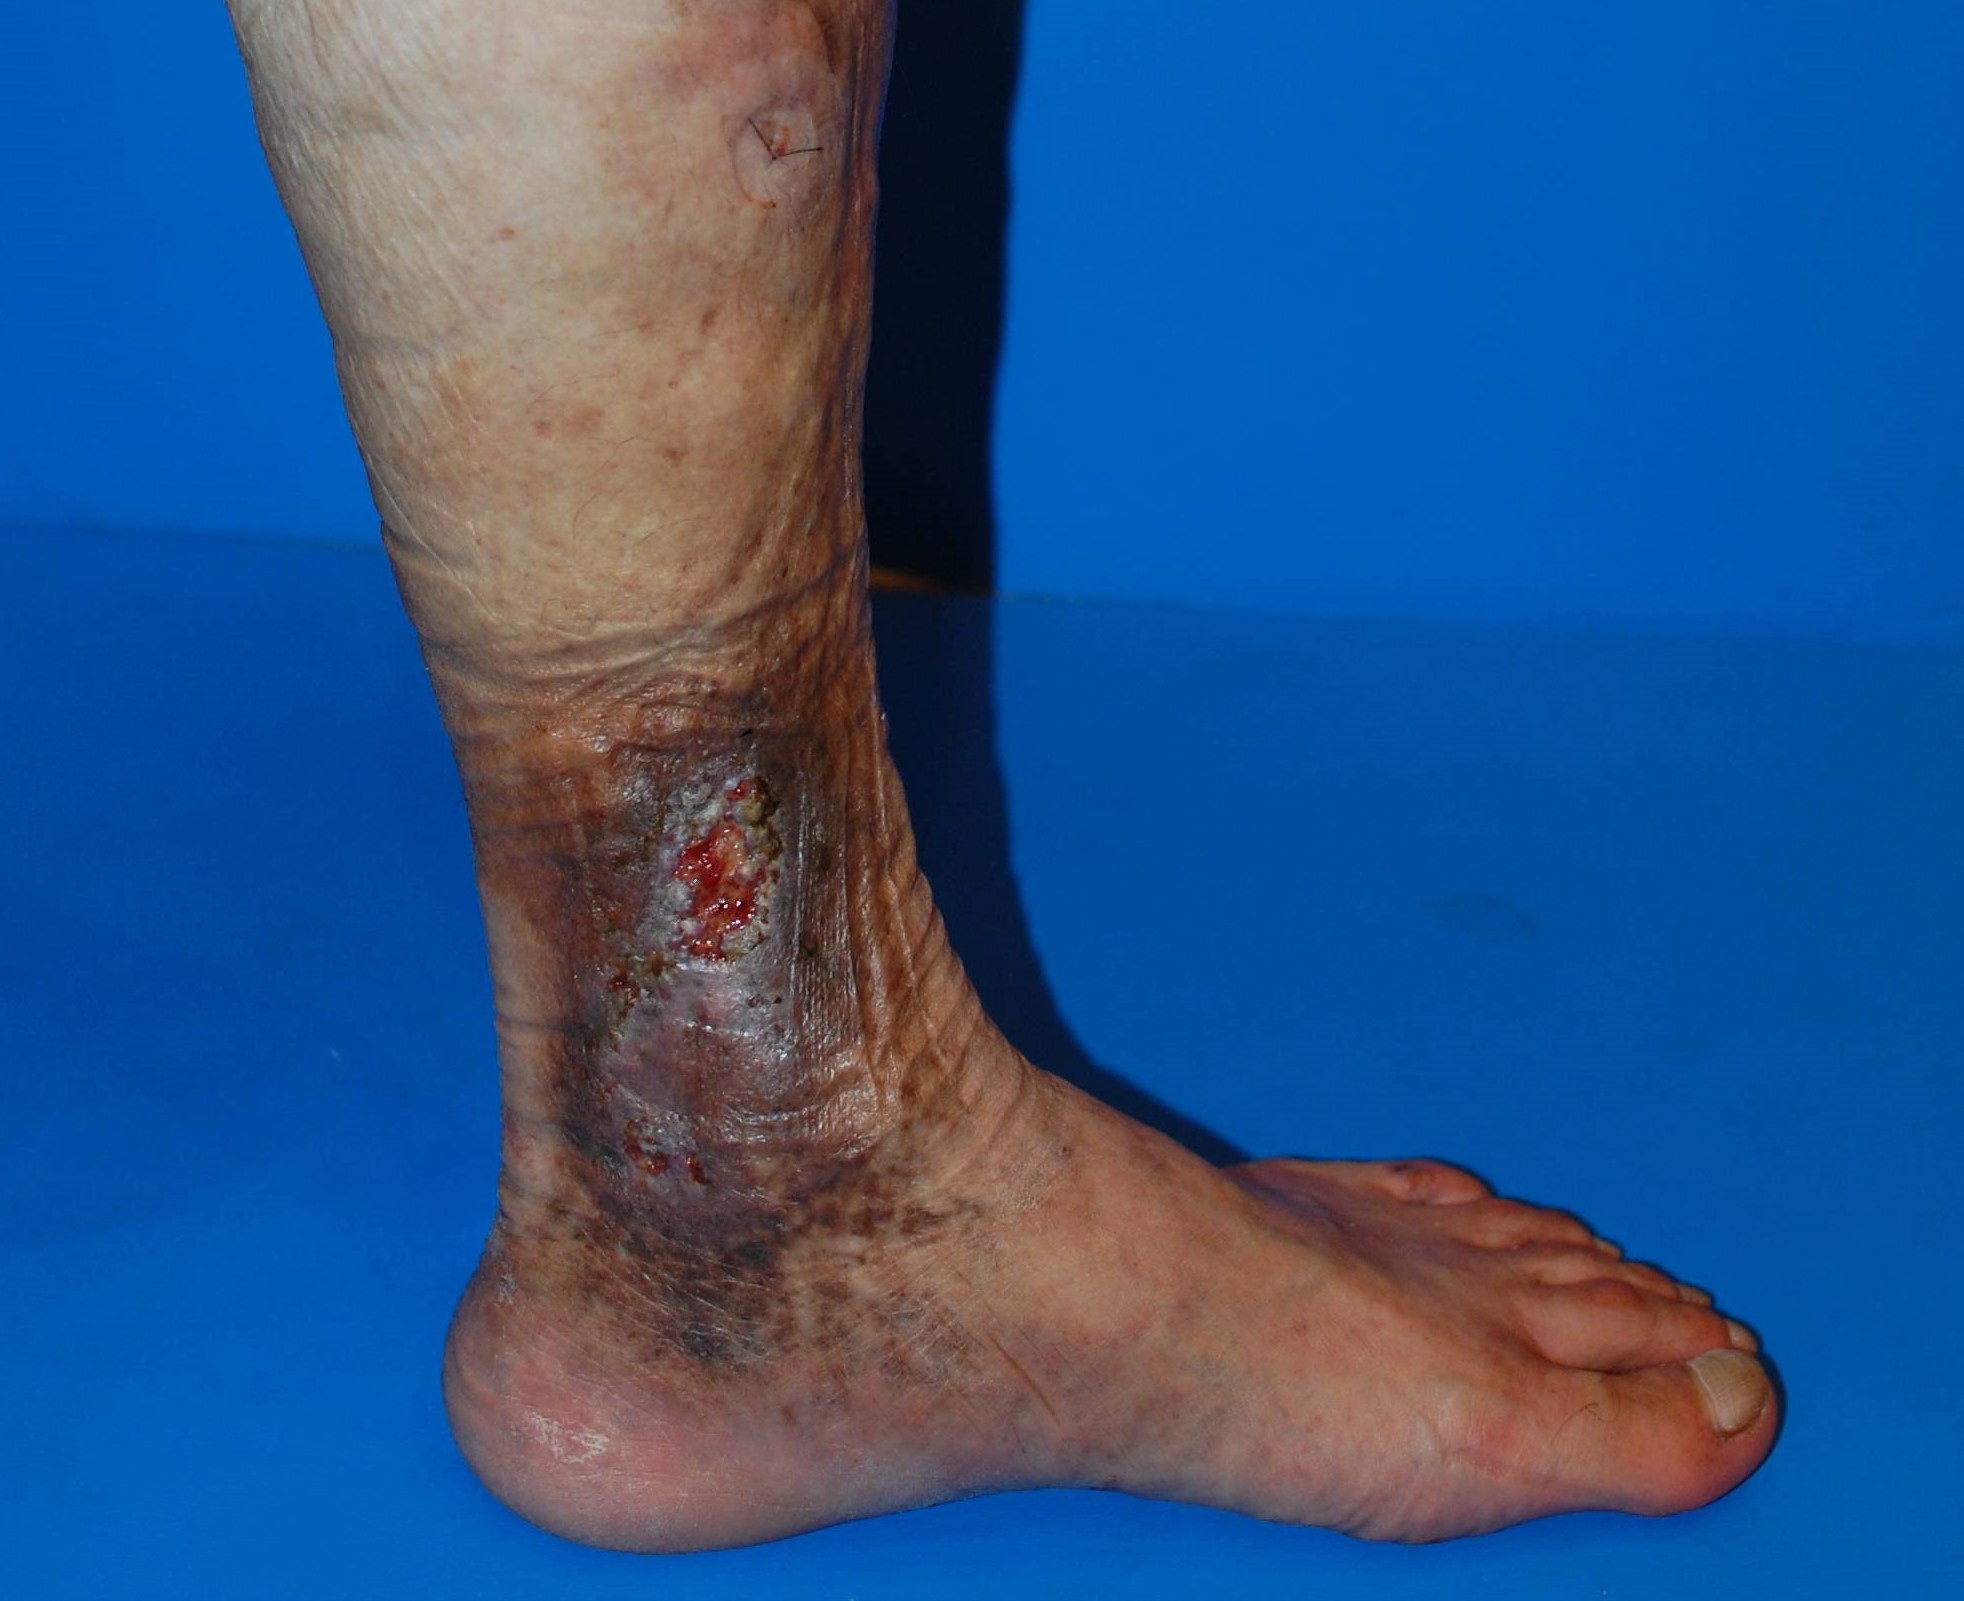

【ステップ4】皮膚潰瘍 ― 強い痛みと治りにくい“最終段階”

痛みが強く、生活に大きな支障をきたします。

- 傷が広がりやすく、治癒に時間がかかる

- 滲出液(じんしゅつえき)が出やすい

- 再発しやすく、治療が長期化しやすい

皮膚潰瘍

潰瘍まで進むと治療に多くの時間と労力がかかり、生活面の負担も大きくなります。

ここまで悪化させないことが最も大切です。